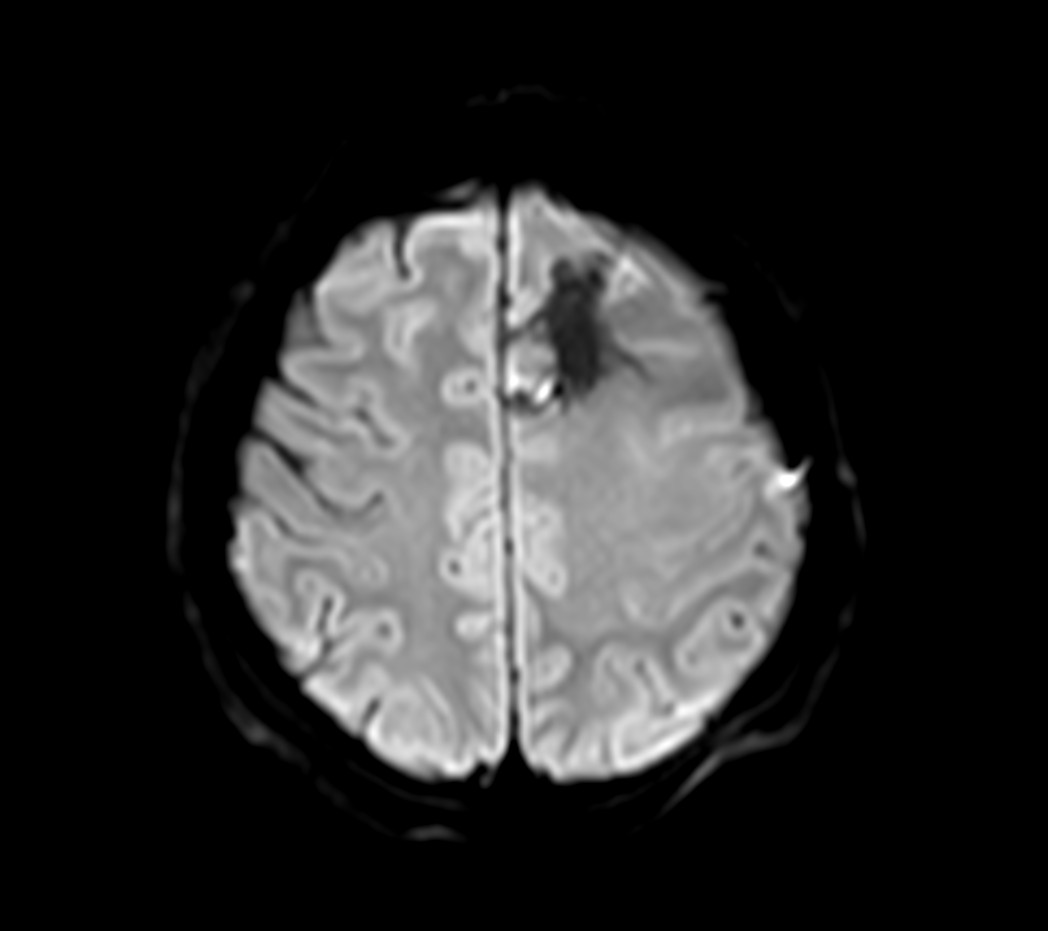

SmartSpeed Precise imaging for brain with glioblastoma

Kyushu University Hospital Japan